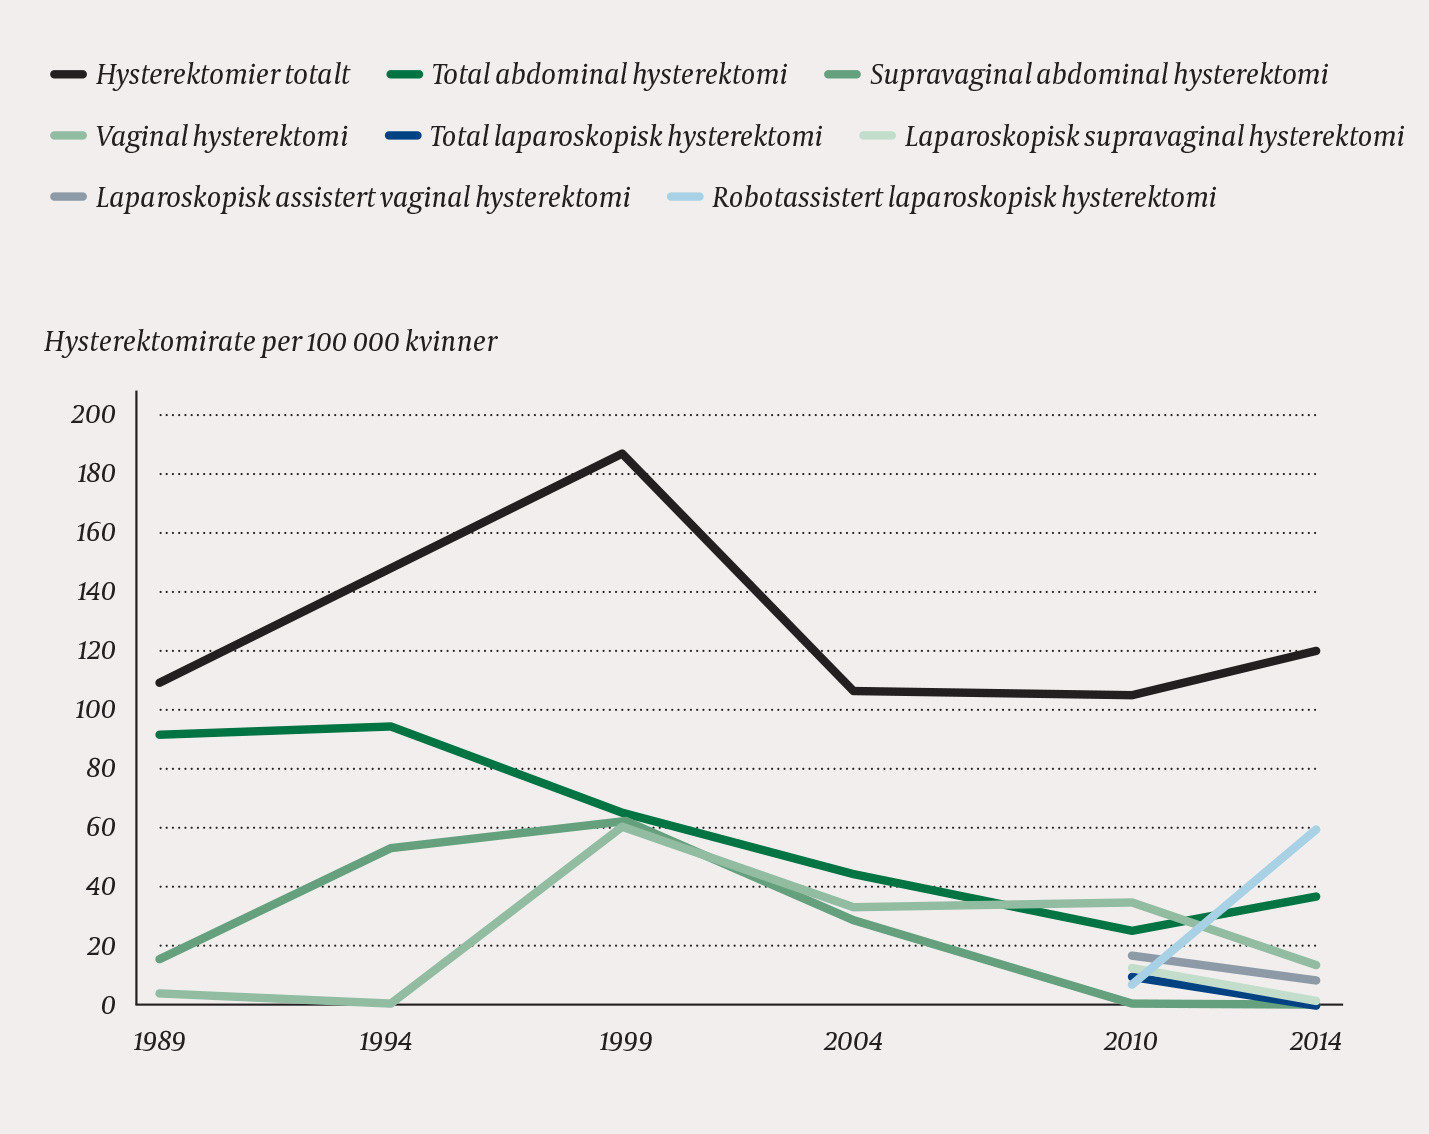

From 1989 to 2014, preoperative diagnosis by dilation and curettage was reduced from 68 % to 4 %, whereas the Pipelle method increased from 8 % to 68 %. In 2014, ultrasound examination was performed in 97 % of patients. While hysterectomies performed with laparotomy fell from 107 in 1989 to 37 per 100 000 women in 2014, vaginal and laparoscopic hysterectomies together increased in the same period from three to 81 per 100 000 women. In 2014, almost half of hysterectomies were performed with robot-assisted laparoscopy. In parallel with the transition from laparotomy to less invasive methods, less bleeding was recorded as well as shorter periods of hospitalization and sickness absence.

Vi identifiserte 947 kvinner som ble operert på benign indikasjon disse seks årene. Av disse hadde vi tilgang til 903 journaler for uthenting av informasjon. Flest kvinner ble hysterektomert i 1999 (186 kvinner per 100 000 kvinneår), hvoretter raten falt med 37 % (til 118 per 100 000) i 2014 (fig 1, tab 1).

Til og med 2004 var laparotomi den vanligste operasjonsmetoden for hysterektomi. I 2010 ble flest operert vaginalt, 35 per 100 000 kvinneår, og 37 per 100 000 ble operert med ulike konvensjonelle laparoskopiske teknikker (fig 1, tab 1). Robotassistert laparoskopisk hysterektomi ble tatt i bruk på St. Olavs hospital i november 2010, og økte til 58 per 100 000 kvinneår i 2014, om lag halvparten av alle hysterektomiene dette året. I samme periode falt raten av konvensjonell laparoskopisk hysterektomi med 76 % til 9 per 100 000 kvinneår og vaginale med 60 % til 14 per 100 000 (fig 1, tab 1).